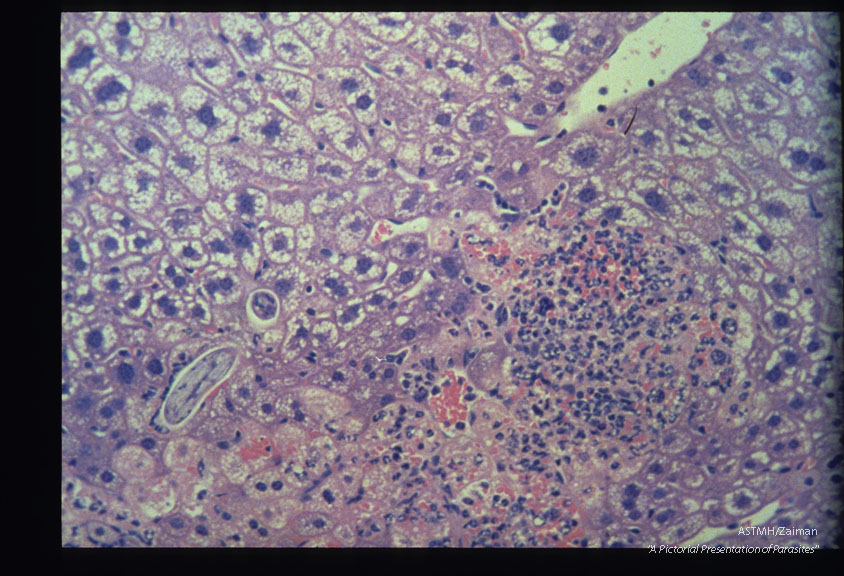

Mouse, BALB/c-Experimental infection as in 1955 Liver. At 48 hours PI this coiled larva, seen in both longitudinal and cross section, is not directly associated with the inflammatory response. HE, x 400.

Description: Mouse, BALB/c-Experimental infection as in 1955 Liver. At 48 hours PI this coiled larva, seen in both longitudinal and cross section, is not directly associated with the inflammatory response. HE, x 400.